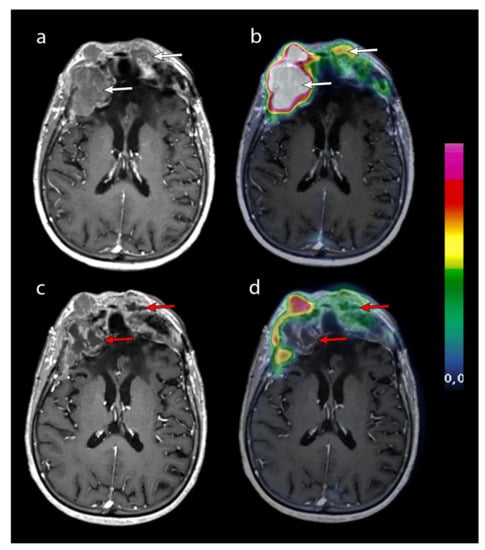

2.2. Imaging

2.4. MRI Response Assessment